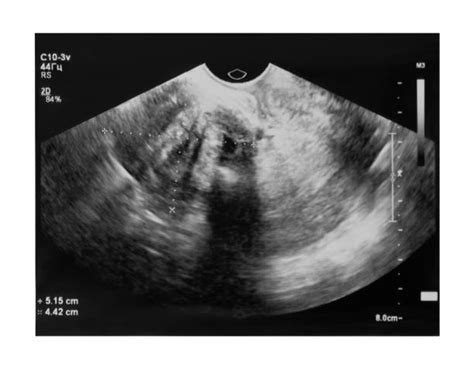

Najčastejším a základným príznakom je objavenie sa abnormálneho krvácania z maternice, najčastejšie u ženy po menopauze. Pri abnormálnom gynekologickom krvácaní je metódou prvej voľby transvaginálne sonografické vyšetrenie (USG). Hrúbka endometria u ženy po menopauze nepresahuje 5 mm.